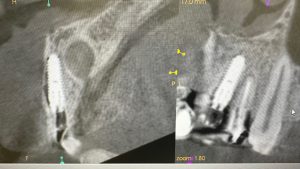

土曜日朝、前歯の抜歯即時

切歯管が近接しているから慎重にがテーマ!

その前に、部分抜歯し唇側束状骨の吸収を防ぐ!